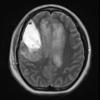

MYELIN (IMMUNE-MEDIATED)

AHL

AHL (7)